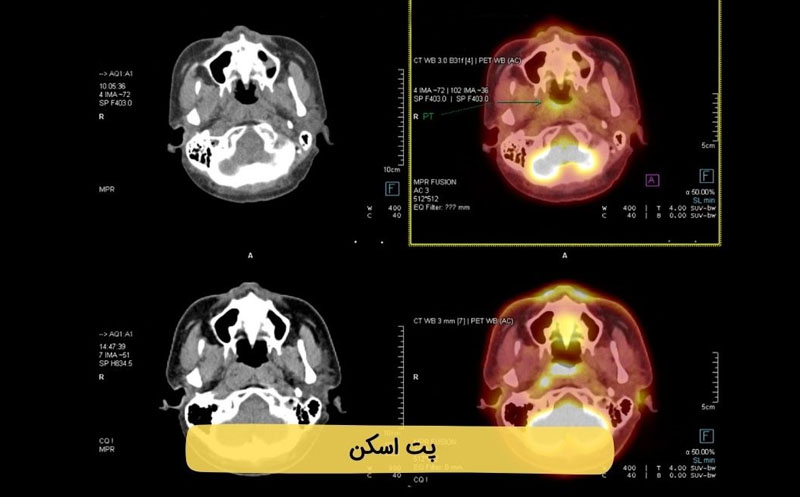

بسیاری از بیماران هنگام مشاهده تصاویر پت اسکن با سوالاتی مانند «نقاط قرمز در پت اسکن چیست؟» یا «آیا هر ناحیه قرمز نشانه سرطان است؟» مواجه میشوند. این نقاط رنگی معمولاً نشاندهنده افزایش مصرف ماده رادیواکتیو و فعالیت بالای سلولی هستند که میتواند به دلایل مختلفی از جمله تومورهای سرطانی، التهاب یا عفونت ایجاد شود. به همین دلیل، تفسیر دقیق عکس پت اسکن سرطانی نیازمند بررسی تخصصی توسط پزشک متخصص پزشکی هستهای است.

در عکس پت اسکن سرطانی (مثلاً تصویر یک PET/CT از تومور) ابتدا مهم است بدانید این تصاویر معمولاً به صورت رنگی با شدت نور متفاوت نمایش داده میشوند که فعالیت متابولیک غیرطبیعی (مثل سلولهای سرطانی) را نشان میدهند.

ویژگیهای عکس پت اسکن سرطانی:

- نقاط روشن (زرد، نارنجی، قرمز) نشان دهنده فعالیت متابولیک بالا و معمولاً نشان دهنده ناحیه سرطانی.

- نواحی تیره یا آبی نشاندهنده فعالیت کم یا بافتهای نرمال.

- اغلب با CT ترکیب میشود (PET/CT) تا محل دقیق ضایعه مشخص باشد

نقاط قرمز در پت اسکن چیست

نقاط قرمز در پت اسکن نشاندهنده نواحی از بدن هستند که در آنها جذب ماده رادیواکتیو بیش از حد طبیعی انجام شده است. در تصویربرداری PET Scan معمولاً از مادهای مانند FDG استفاده میشود که سلولهای فعالتر آن را بیشتر جذب میکنند. به همین دلیل، این نواحی در تصویر بهصورت نقاط قرمز، نارنجی یا زرد دیده میشوند.

در بسیاری از موارد، نقاط قرمز در پت اسکن میتوانند نشانه افزایش فعالیت متابولیکی سلولها باشند؛ حالتی که اغلب در سلولهای سرطانی مشاهده میشود. سلولهای سرطانی به دلیل رشد سریع، مصرف انرژی بالاتری دارند و همین موضوع باعث روشنتر دیده شدن آنها در تصویر پت اسکن میشود. با این حال، مشاهده نقاط قرمز همیشه به معنای سرطان نیست.

نکته مهم این است که برخی از اندامهای بدن مانند مغز، قلب، کلیهها و مثانه بهطور طبیعی جذب بالایی دارند و وجود نقاط قرمز در این نواحی کاملاً طبیعی است. همچنین عواملی مانند التهاب، عفونت، فعالیت عضلانی، یا حتی زمان نزدیک به جراحی میتوانند باعث ایجاد نقاط قرمز در پت اسکن شوند. به همین دلیل، تفسیر نقاط قرمز در پت اسکن باید همراه با بررسی محل، شدت جذب (SUV) و شرایط بالینی بیمار انجام شود.